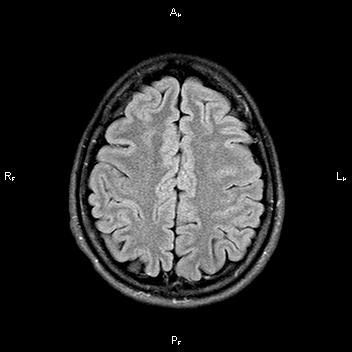

При сканировании головного мозга в нескольких режимах в кортикальных отделах левой теменной доли был обнаружен лакунарный инфаркт диаметром 7мм. Острый инфаркт хорошо виден на ДВИ (импульсная последовательность, доступная в томографах экспертного класса), но плохо виден в режиме с подавлением сигнала от свободной жидкости.

После проведенного лечения состояние пациентки улучшилось. На МР-томографии спустя 3 месяца заметна положительная динамика.